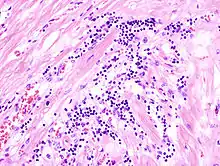

Acute myocardial infarction

Der Myokardinfarkt muss mind. 6 - 12 Stunden überlebt werden, bevor er morphologisch sichtbar wird!

Mikro: Koagulationsnekrose, Einblutungen. Die Myozyten zeigen eine verstärkte Eosinophilie und Kontraktionsbanden quer durch die Herzmuskelfasern. Typische Zellparameter wie Querstreifung, Zellkerne und Zellgrenzen gehen verloren. Das Infarktareal wird von einer Hyperämischen/hämorrhagischen Randzone begrenzt. Im Verlauf zunehmende leukozytäre Demarkation und Phagozytose des nekrotischen Gewebes, sowie Einwanderung von Fibroblasten mit Ausbildung eines narbigen Ersatzgewebes.

![]() Myokardinfarkt 7. Tag (Abräumphase), Sektionspräparat, H&E. |